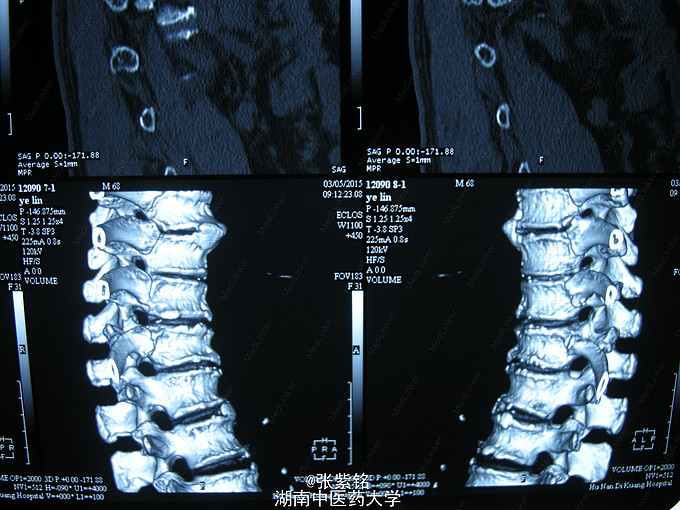

查体见:左额部可见约2cm*2cm皮下血肿,并可见一不规则伤口约2cm,伴活动性出血。脊柱驼背畸形,胸椎后凸,头部前伸体态;颈、腰部旋转活动不能,腰部于L3-5椎体棘突处压痛明显,双下肢肌力、肌张力正常。左肩部关节明显肿胀,可扪及空虚感;局部压痛明显,左Dugas征阳性,左肩关节主动上举,外展,后伸,内收活动受限;被动活动患处疼痛加剧,左侧桡动脉搏动可扪及,皮肤感觉正常,左肘、腕及各指间关节血运感觉活动正常。 X线片示:左肩关节脱位,左肱骨外科颈骨折,左肱骨大结节撕脱性骨折。

1、左肩关节脱位伴大结节撕脱性骨折,2、左肱骨外科颈骨折,3、头部外伤、头面部皮肤裂伤,4、强直性脊柱炎。 1、清创缝合伤口。2、患肢制动,消肿,止痛等对症处理。3、完善相关检查。4、择期行手术治疗及术后对症处理。